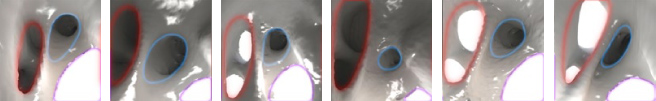

Below: multiple endoscopic renderings of LAA ostia (blue outline), pulmonary veins (red outline) and the mitral valve (removed, purple outline), illustrating the wide variety of often non-circular shapes.